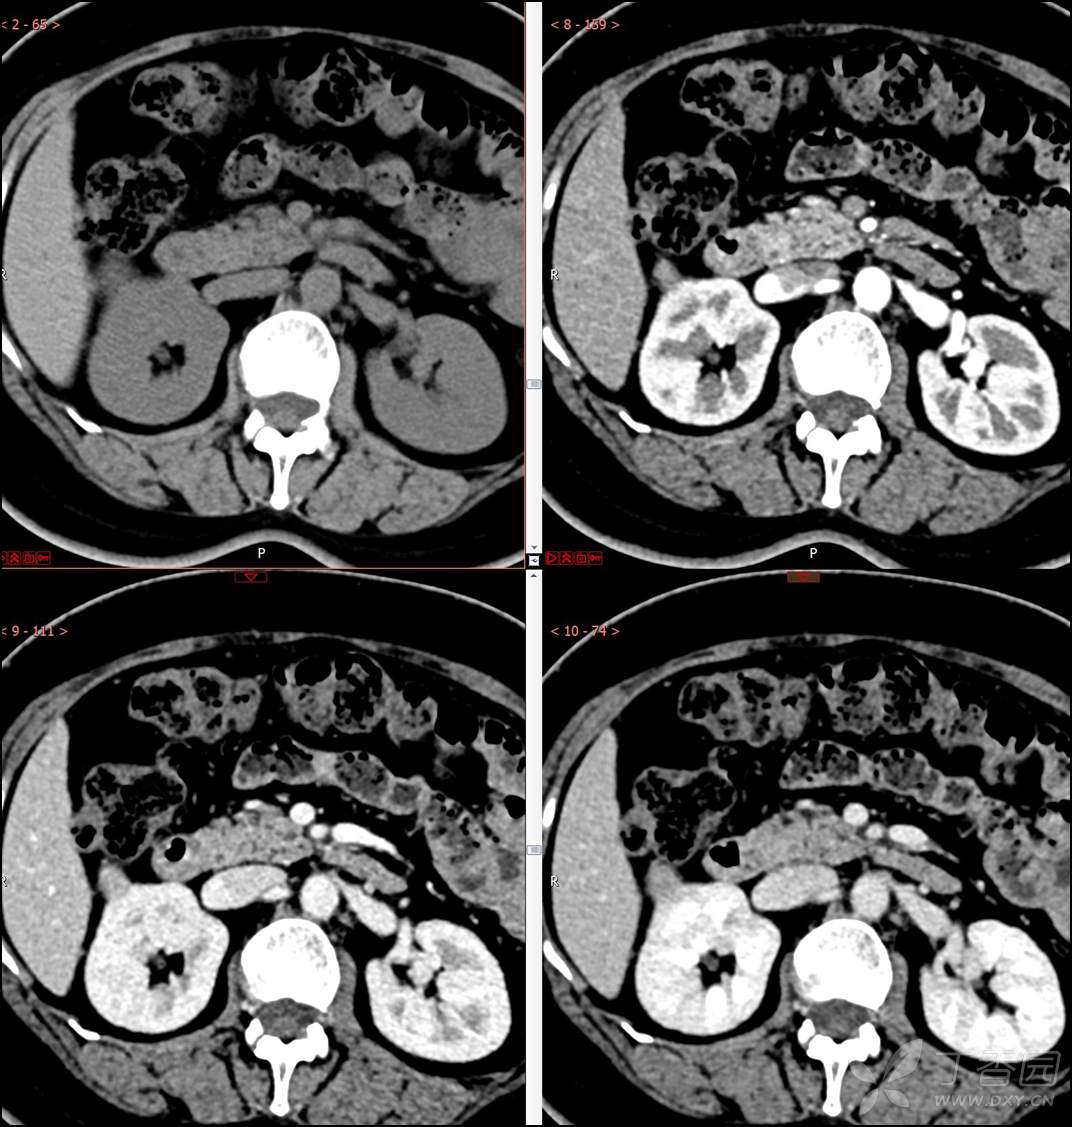

【影诊笔记516】中年女性,检查发现肾占位2周就诊~『嗜酸细胞腺瘤』

主诉:检查发现肾占位2周

简要病史:患者2周前体检发现肾实质性占位,无腰痛,无血尿,无尿频、尿急、尿痛,无发热,在外未行特殊治疗。患者为行进一步治疗就诊于我院,门诊以“肾占位性病变 ”收入我科,患者自发病以来,神志清,精神可,小便如上所述,大便正常,体重无显著变化。